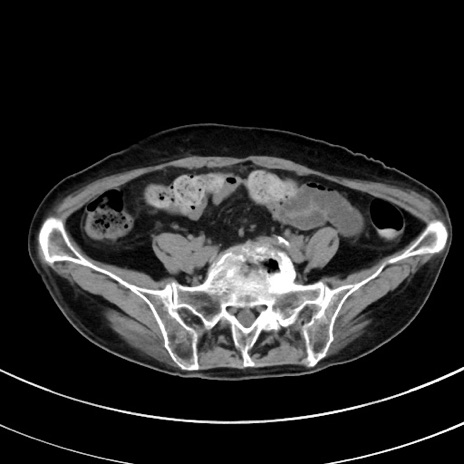

症例33(横断像)

【症例】70歳代 女性

【主訴】心窩部痛

【現病歴】延髄病変の精査・加療にて神経内科入院中。本日より心窩部痛あり。

【身体所見】右下腹部を中心に圧痛と反跳痛あり。